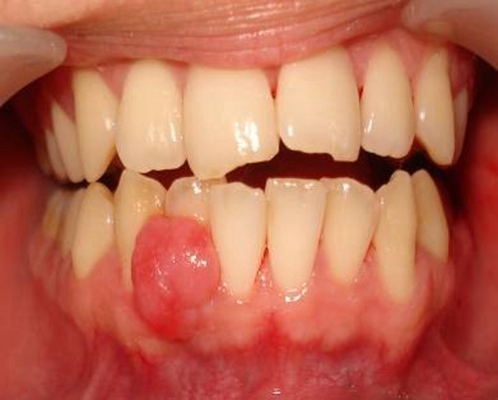

長期服用某種藥物可能引起牙齦增生,臨床表現(xiàn)為牙齦邊緣和牙齦乳頭增生,從_初的小球狀逐漸融合、增大、直到覆蓋部分牙冠。增生部分大多質(zhì)地堅韌,略有彈性,一般不痛、不出血。臨床上鈣離子拮抗劑、抗癲癇藥、免疫抑制劑是引起牙齦增生_常見的藥物。